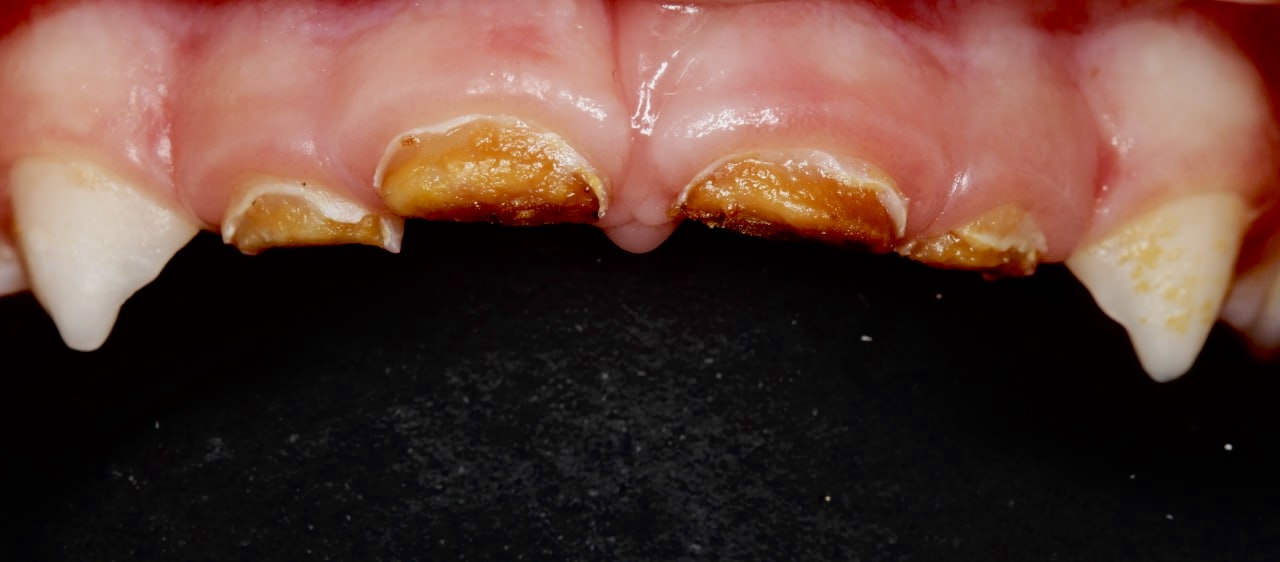

Дитина звернулася до нашої клініки разом із батьками зі скаргами на значне руйнування передніх зубів та неможливість відкушувати їжу.

Під час огляду було встановлено, що чотири передні молочні зуби зруйновані настільки, що не могли виконувати свою функцію та потребували комплексного відновлення.

Як проходило лікування

З огляду на:

• вік дитини,

• обсяг і складність лікування,

• необхідність забезпечити комфорт і безпеку, було прийнято рішення провести лікування в умовах загального знеболення.

Під час лікування передні зуби були відновлені за допомогою цирконієвих коронок, що дозволило:

• відновити можливість нормально відкушувати їжу,

• захистити зуби від подальшого руйнування,

• повернути естетику усмішки,

• зберегти зуби до моменту їх природної зміни.